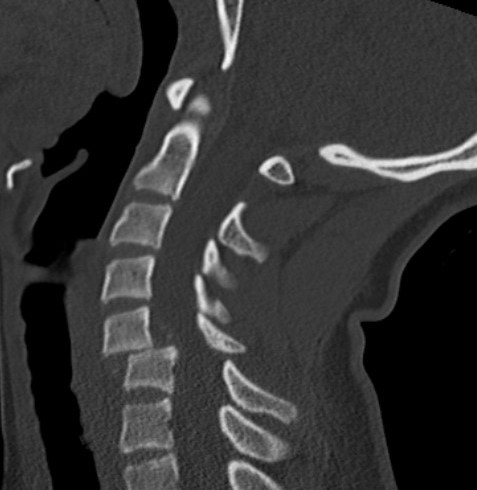

Unilateral facet joint dislocation on CT

>50% forward subluxation

Bilateral jumped facets on CT